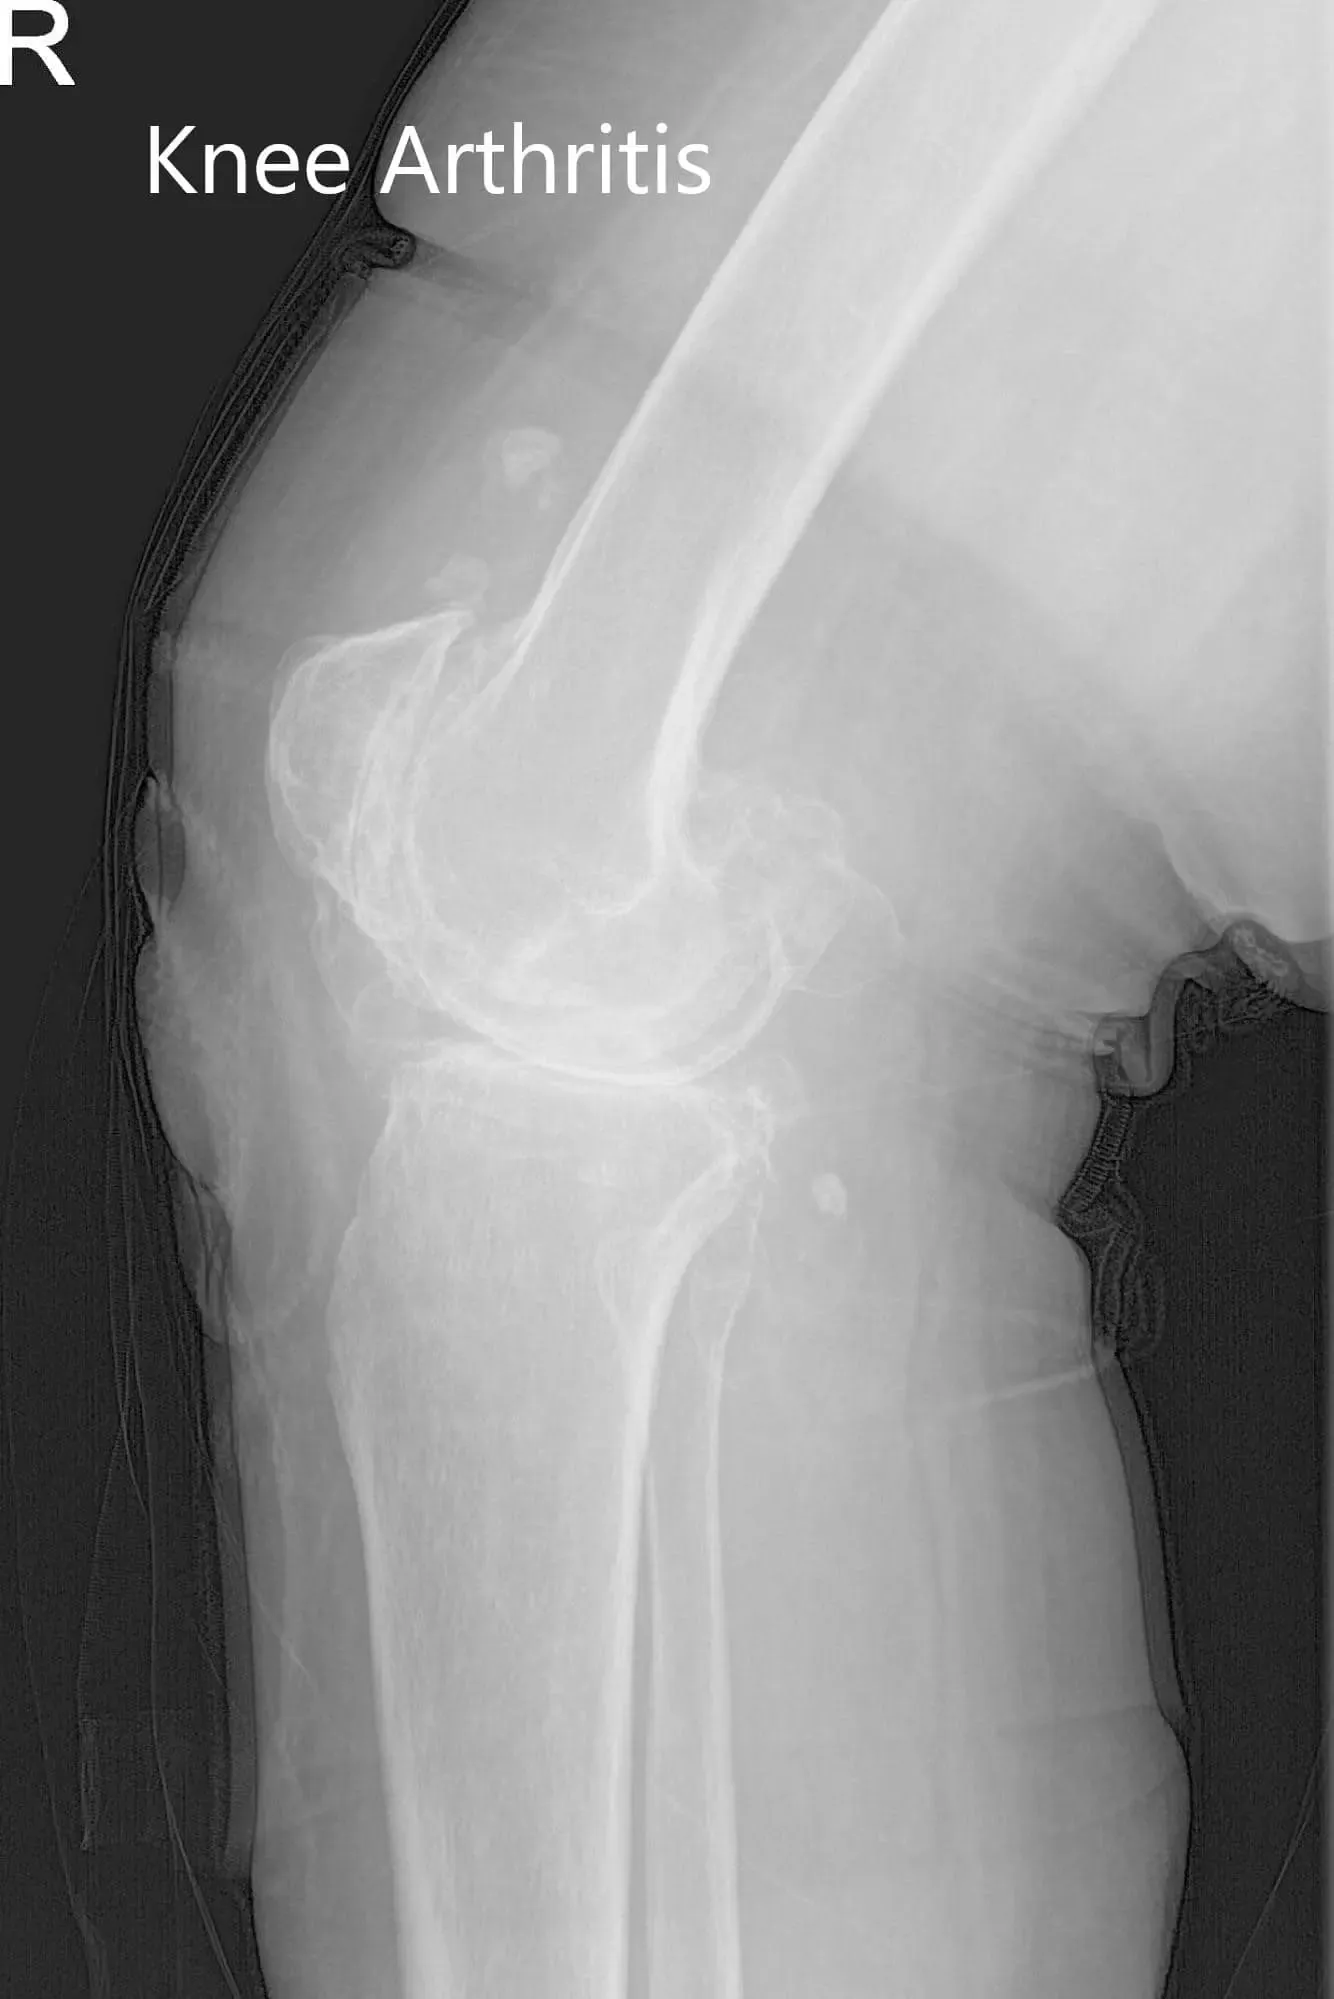

Preoperative X-ray of the right knee showing AP and lateral views

His physical examination revealed severe arthritis of the bilateral knees. There was mild swelling bilaterally with no rise in temperature or erythema. The overlying skin of bilateral knees was normal. There was tenderness on the medial joint line and patellar facet (right greater than left).

Genu varus deformity was present with a restricted range of motion due to pain (right – 0 to 95 degrees and left – 0 to 100 degrees). There was no coronal, sagittal or rotational plane instability or laxity. The distal neurological examination was normal bilateral. Distal lower extremity pulses were 2+ and palpable.

His imaging studies revealed severe tricompartmental osteoarthritis of the bilateral knee joint. After careful consideration of his medical conditions and needs, he was advised bilateral custom total knee replacement. He was made aware of the increased risk associated with bilateral surgery. Alternatives, risks, and benefits were discussed in detail with him and his son. They agreed for the procedure.